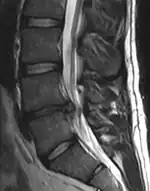

- Magnetic resonance imaging is the gold standard study for confirming a suspected LDH. With a diagnostic accuracy of 97%, it is the most sensitive study to visualize a herniated disc due to its significant ability in soft tissue visualization. MRI also has higher inter-observer reliability than other imaging modalities. It suggests disc herniation when it shows an increased T2-weighted signal at the posterior 10% of the disc. Degenerative disc diseases have shown a correlation with Modic type 1 changes. When evaluating for postoperative lumbar radiculopathies, the recommendation is that the MRI is performed with contrast unless otherwise contraindicated. MRI is more effective than CT in distinguishing inflammatory, malignant, or inflammatory etiologies of LDH. It is indicated relatively early in the course of evaluation (<8 weeks) when the patient presents with relative indications like significant pain, neurological motor deficits, and cauda equina syndrome. Diffusion tensor imaging is a type of MRI sequence used for detecting microstructural changes in the nerve root. It may be beneficial in understanding the changes that occur after herniated lumbar disc compresses a nerve root, and might help in differentiating the patients that need surgical intervention. In patients with a high suspicion of radiculopathy due to lumbar disc herniation, yet the MRI is equivocal or negative, nerve conduction studies are indicated.[44] T2-weighted images allow for clear visualization of protruded disc material in the spinal canal.

MRI scan of cervical disc herniation between C5 and C6 vertebrae

MRI scan of large herniation (on the right) of the disc between L4 and L5 vertebrae

A rather severe herniation of the L4–L5 disc

Example of a herniated disc at L5–S1 in the lumbar spine